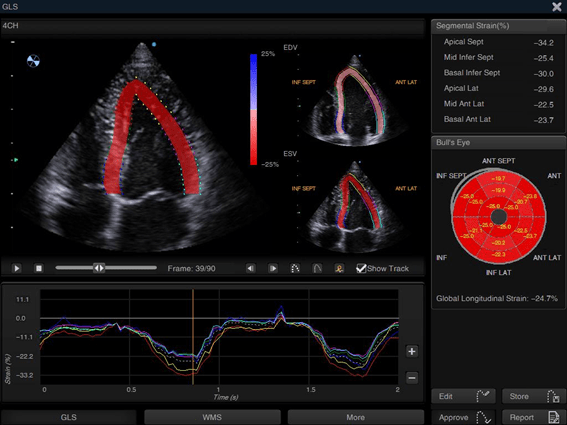

- Strain Rate

- Auto SG

- Auto EF